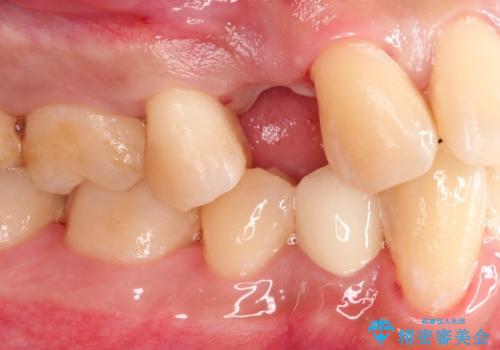

- 歯根破折により抜歯となってしまった患者様です。

インプラントによる咬合回復を行いました。

インプラントによる治療は隣在歯を削らずに咬合回復できるという利点があります。